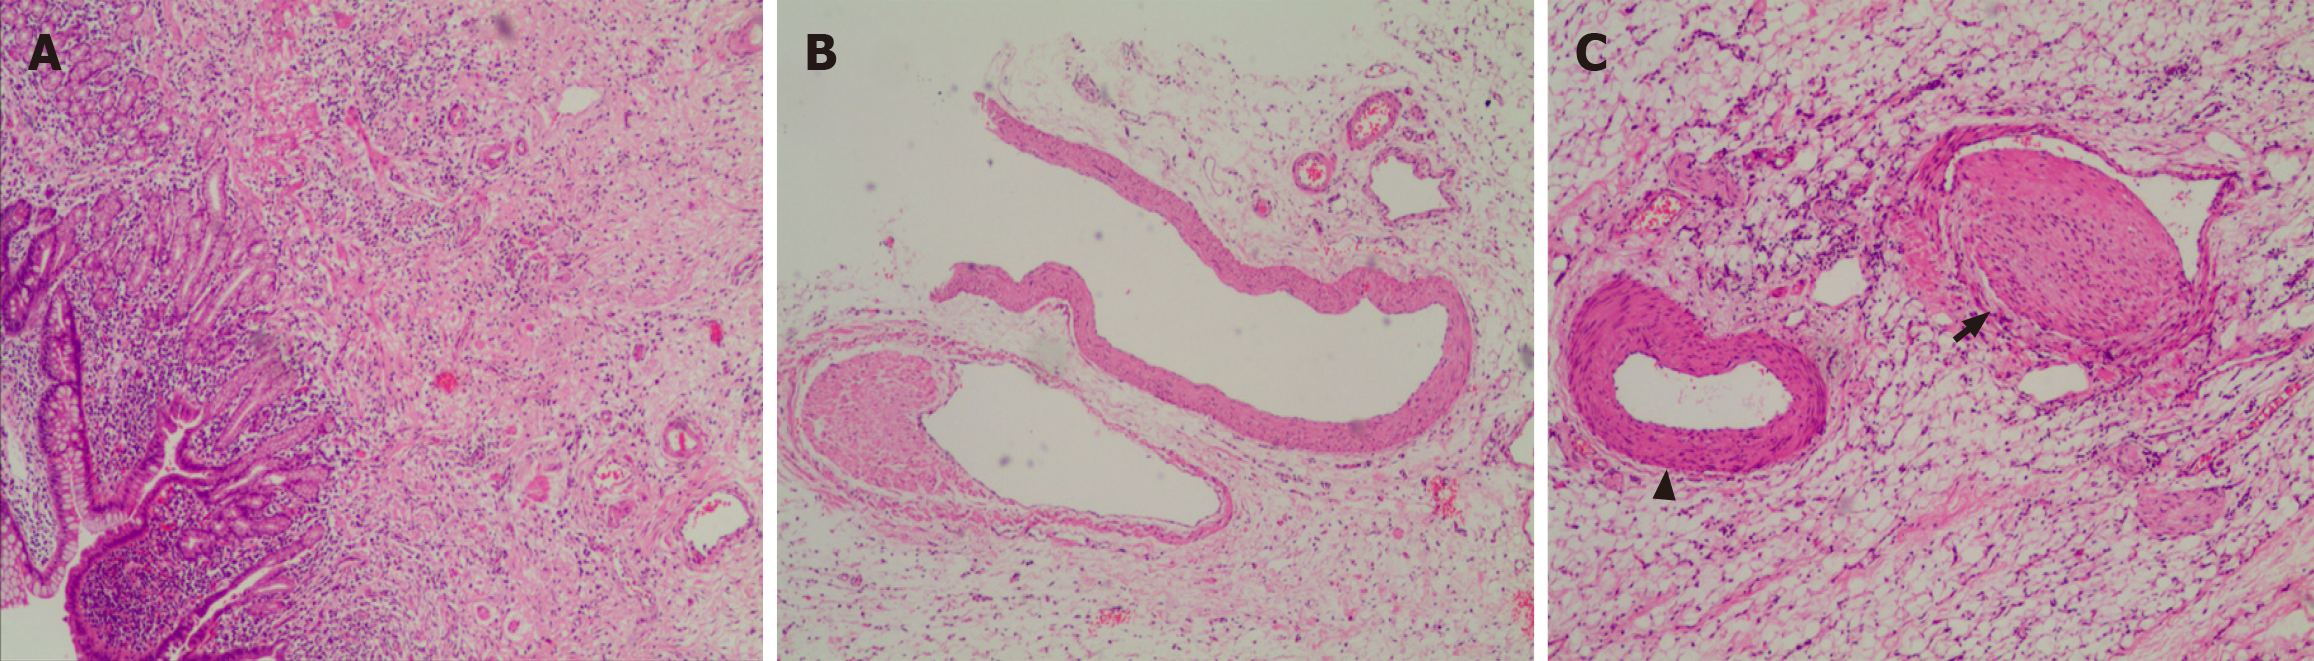

Figure 4 Microscopic observation of lesions.

A: Small intestinal villous atrophy with extensive pyloric gland metaplasia, submucosal fibrous tissue proliferation, and infiltration of lymphocytes, plasma cells, and granulocytes in both the mucosa and submucosa, with focal abscess formation and approximately 15 eosinophils per high-power field. No typical granulomatous lesions were observed on the slide [hematoxylin & eosin (H&E) 20 ×]; B: Irregular proliferation of smooth muscle cells in mesenteric veins, eccentric hyperplasia (H&E 100 ×); C: Mesenteric vein intimal hyperplasia (arrow), lumen stenosis, no thrombus, and no obvious abnormality in the accompanying artery (triangle) (H&E 100 ×).